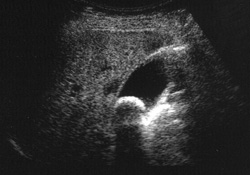

「超音波検査」とは、超音波(耳では聞こえない、高い周波数の音)を利用して体内を観察する検査法です。超音波は「超音波探傷検査」として建築の分野でも利用されますが、人体に無害とされるため医療の現場で活躍しています。疾患の発見や精密検査としての画像診断としても用いられますが、人間ドックや各種検診、胎児を診るためにも利用されているのは有名なのではないでしょうか。

超音波検査によって、臓器の大きさや腫瘍、結石の有無がわかります。また、脂肪肝や肝硬変などの有無や程度も調べることが可能です。